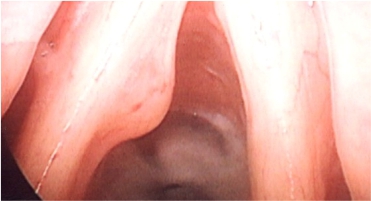

1. Nasal Endoscopy

2. Nasopharyngoscopy

3. Laryngoscopy